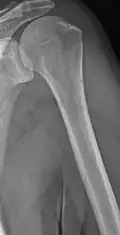

Multiple myeloma in the upper arm -

Humerus with multiple myeloma lesions -

Same humerus before, with just subtle lesions